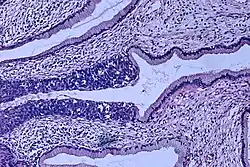

Histologicznie CIN manifestuje się zaburzeniem różnicowania komórek nabłonka wielowarstwowego płaskiego, zmianą morfologii pojedynczych komórek i zaburzeniem budowy architektonicznej całego nabłonka. Komórki prawidłowego nabłonka mają okrągłe, równe jądra o drobnoziarnistej chromatynie rozproszonej regularnie. W nabłonku z cechami neoplazji śródnabłonkowej (CIN) stwierdza się cechy atypii: powiększenie jąder komórkowych, ich hiperchromazję, polimorfizm kształtu, wielkości oraz zabarwienia. Częste są komórki dwu- i wielojądrowe. Organizacja nabłonka jest zaburzona. W miarę nasilenia zmian morfologicznych wzrasta stopień CIN jaki przypisuje się tym zmianom. Ponadto, w komórkach nabłonka zainfekowanego wirusem brodawczaka stwierdza się koilocyty – komórki z dużą jasną wodniczką, silnie zaznaczoną hiperchromazją i charakterystycznym, "pomarszczonym" obrysem. W zainfekowanym HPV nabłonku występuje parakeratoza, a granice międzykomórkowe są wyraźnie widoczne i pogrubiałe. Komórki nabłonka z cechami CIN często "tapetują" cewki gruczołowe, co należy w ocenie histologicznej różnicować z naciekaniem podścieliska.